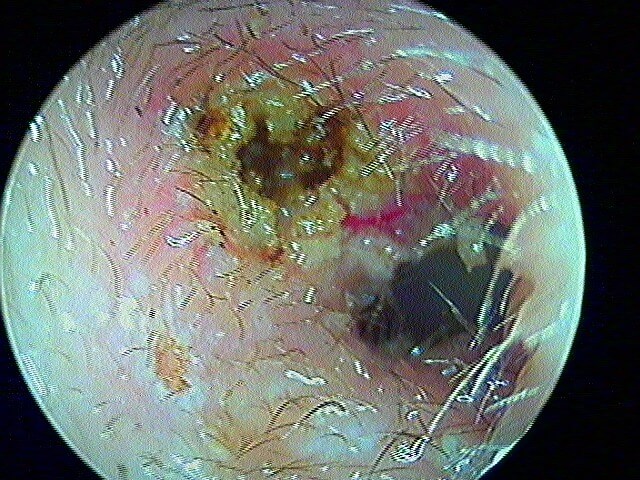

2/5 otite externe mycotique ou otomycose

Dans ma pratique, je vois plus d'otomycose à Aspergillus niger, très caractéristique avec ces points noirs.

La même oreille après aspiration: